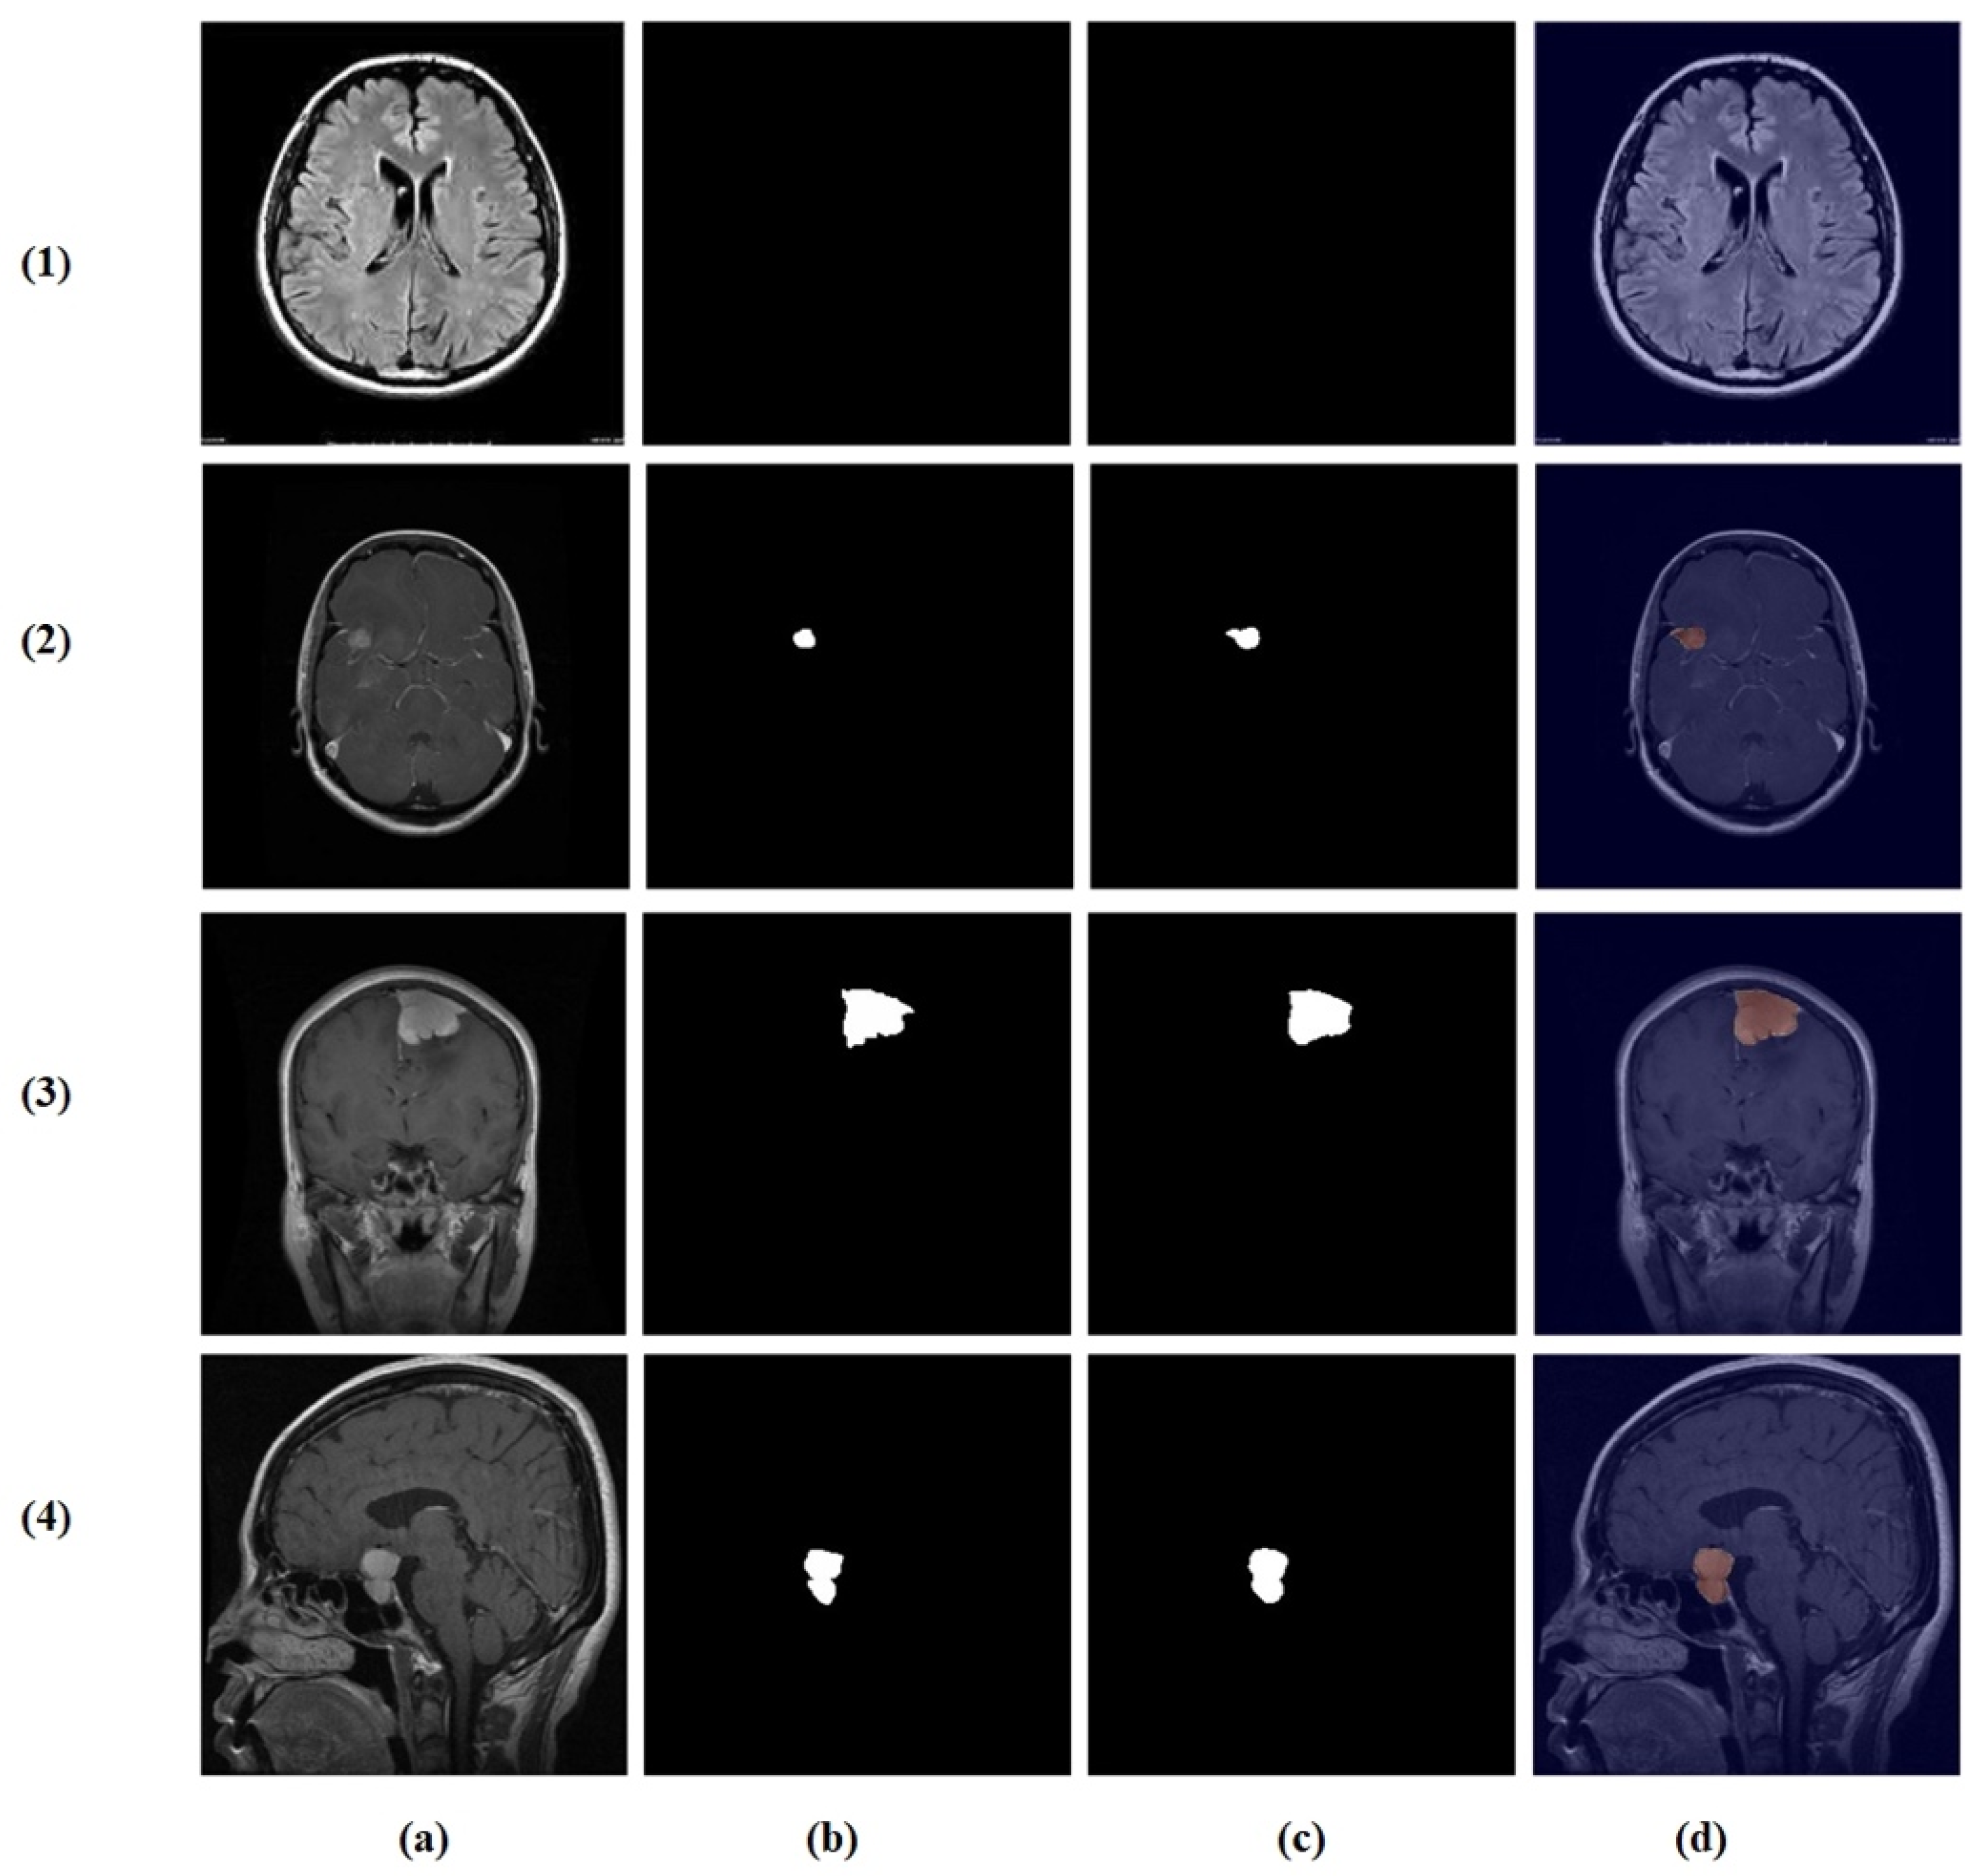

4.7. Feature Learning Analysis

Figure 12, Figure 13, Figure 14 and Figure 15 present Grad-CAM visualizations that trace the hierarchical feature learning of the proposed model across the four classes. Columns are organized as (a) input, (b) high-level features, (c) mid-level features, and (d) low-level features. In (d), the network emphasizes primitive cue edges, intensity transitions, and fine textures capturing sulcal boundaries, skull edges, and generic tissue patterns. Progressing to (c), activations become more structured and context-aware, highlighting coherent anatomical regions and diffuse hyperintense areas that provide spatial context for lesion localization. At (b), class-discriminative focus emerges with responses that contract tumor-centric hotspots for glioma and meningioma and to the sellar region for pituitary cases, while no_tumor images exhibit suppressed high-level responses, reflecting the model’s rejection of false lesion cues. This bottom-to-top progression from generic edges to task-specific evidence explains the model’s improved decision reliability and aligns with the multi-task design that encourages precise, clinically meaningful attention.

Visual representation of feature activations in meningioma tumor cases. (a) input, (b) low-level features, (c) mid-level features, and (d) high-level features.

Figure 15.